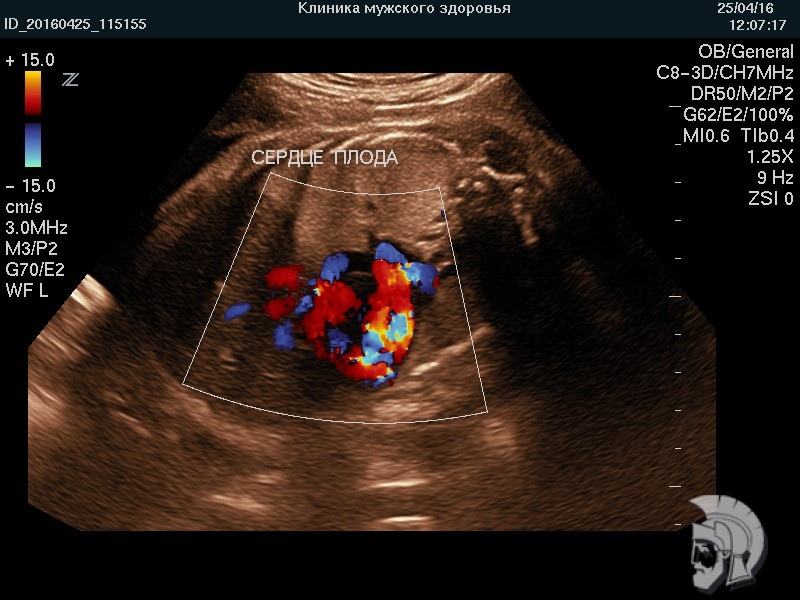

Обратите внимание на совершенное качество фото УЗИ плода, свидетельствующих об экспертном классе аппаратов УЗИ!

Использование ультразвуковых аппаратов экспертного класса с режимами энергетического допплера и цветового ДОППЛЕРа позволяет врачам Курортной клиники мужского здоровья выявить пороки развития плода, маловодие и многоводие, нарушение МППК угрозу прерывания беременности на самых ранних этапах формирования.

| Фото беременности. Сердце плода 20 недель. Исследование структуры сердца в режиме цветового допплера | ![]() |